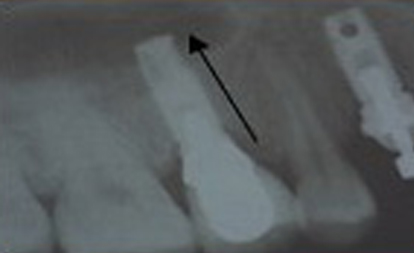

Dr. Ghayoumi may recommend sinus lift and bone graft if a patient does not have enough bone to secure a dental implant in the back areas of the upper jaw. When teeth are lost in these areas, the sinuses often expand and compromise dental implant placement.

A sinus augmentation lifts the maxillary sinus to make room for more bone. This stimulates new bone formation, providing a stable foundation for dental implants.

This surgery is necessary when there is insufficient bone in the maxilla, particularly when the sinus floor or Schneiderian membrane needs to be elevated, requiring bone grafting.